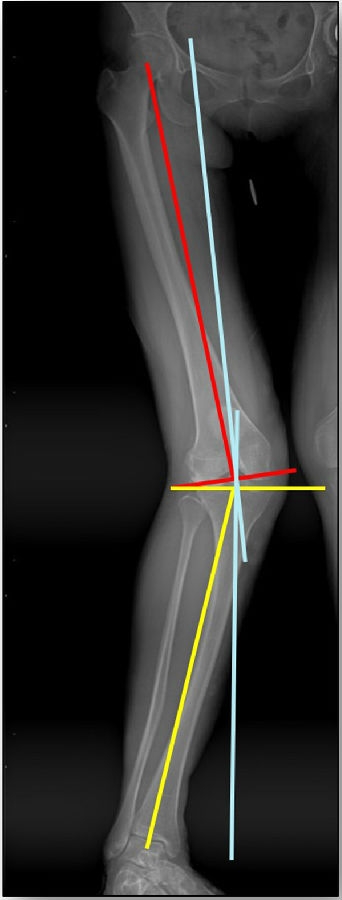

以两例病例展示术前设计的五步。患者一,女性,42岁,左膝疼痛2年,加重1年。

步骤一:判断内外翻畸形

画下肢机械轴,股骨头中心链接踝关节中心判断患者为内翻畸形还是外翻畸形。此患者为外翻畸形。

步骤二:判断畸形部位

量股骨远端外侧角和胫骨近端内侧角,判断畸形在股骨、胫骨还是关节内。此患者股骨侧有畸形,LDFA=76°,MPTA=81°,无关节内畸形。

步骤三:设定目标力线

以关节线为基准参考线,设定目标力线与关节线垂直。

步骤四:确定合页位置和截骨线方向

此患者计划股骨内侧闭合楔,胫骨内侧开放楔。

步骤五:Miniaci法测量角度

以股骨侧合页为旋转中心,以股骨头中心到合页的距离为半径,进行旋转,直到该线段与目标力线相重合,此时重合角度即为股骨需要闭合的角度,同时胫骨侧也能计算出开放的角度。此患者需要股骨闭合14°,胫骨开放8°。